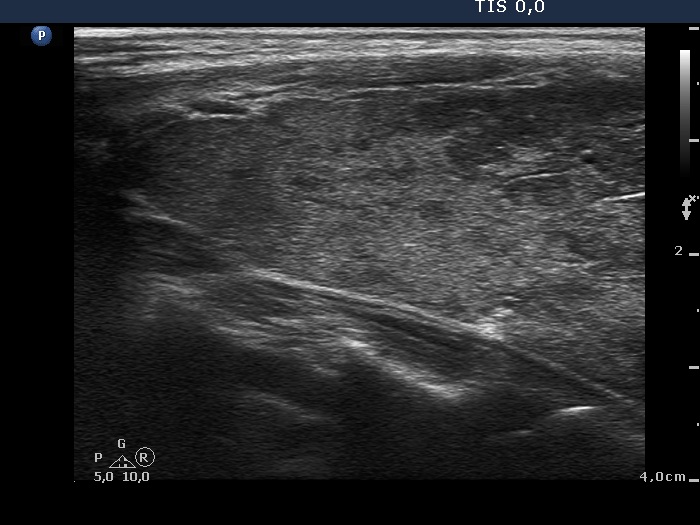

One month after surgery (second row of images):

Clinical data: The patient had no complaints.

Palpation: There was a relatively large, painless mass in the left thyroid bed.

Result of blood test: euthyroidism on daily 125 microgram levothyroxine (TSH 0.87 mIU/L).

Ultrasonography. The thyroid parenchyma was replaced by regenerative tissue. There was a cystic lesion in the left thyroid bed with a maximal diameter of 23 mm.